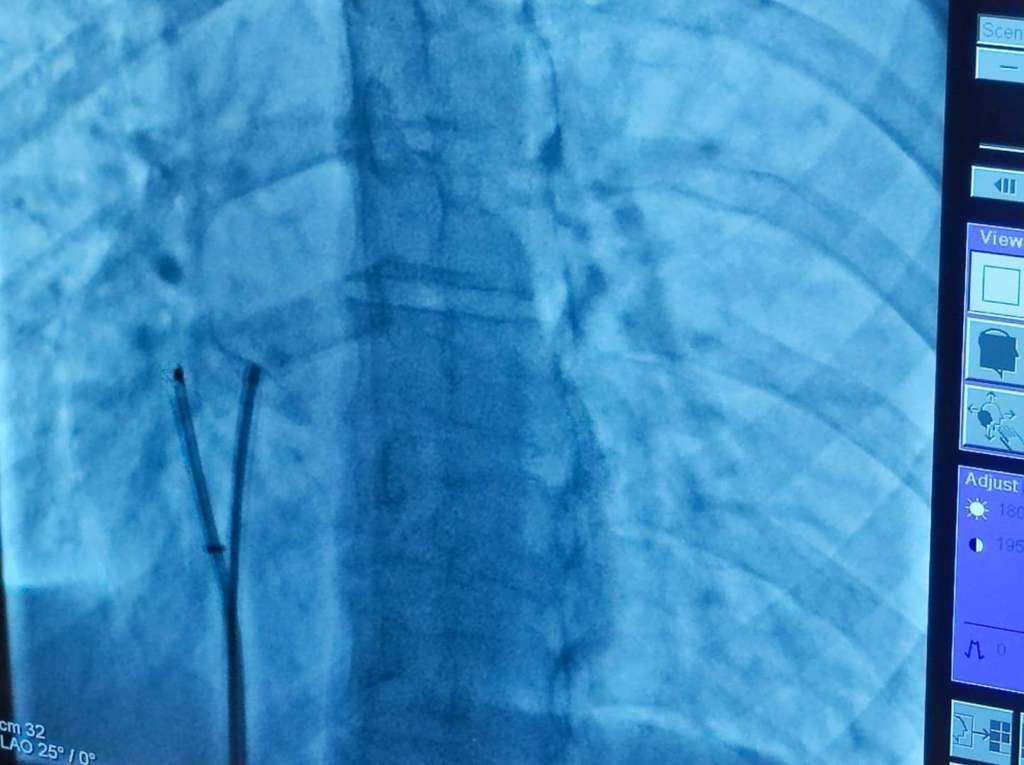

Il Centro, tecnologicamente all’avanguardia, fortemente voluto dal Direttore Generale dell’Azienda Sanitaria Locale di Avellino, Dott. Mario Nicola Vittorio Ferrante, e diretto dal Dott. Vittorio Ambrosini, ha eseguito in 20 giorni dalla sua inaugurazione oltre 80 procedure, tra angiocoronarografie ed angioplastiche coronariche di cui numerose per trattamento di Sindromi Coronariche Acute (Infarto del miocardio).

Nel corso della seduta sono stati eseguiti, con pieno successo, numerosi interventi di chiusura percutanea di vizi cardiaci congeniti, con tecniche percutanee mininvasive tra cui monitoraggio ecocardiografico intracardiaco, in pazienti di età compresa dai 20 ai 52 anni, provenienti sia dal territorio che da fuori regione.